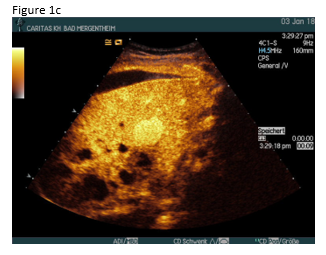

A 49 year old patient was admitted to the hospital for sepsis and shock of unknown origin. The patient presented with signs of sepsis and hemodynamic instability that justified an urgent approach including complex intensive care and intubation. Bedside ultrasound (US) found ascites and an abscess in the right liver lobe (9 cm) (Figure 1a). The patient was treated with broad-spectrum antibiotics and puncture and drainage of the abscess (Figures 1 a-c and 2 a-b). In addition, a biopsy was taken from the periphery of the lesion. A few days after the removal of the drainage the patient presented with a progressive elevation of liver enzymes. US revealed a cystic lesion measuring 30 mm that was proximal to the drained abscess (Figure 1a). Color Doppler Imaging (CDI) showed arterial flow inside the lesion, and contrast enhanced ultrasound (CEUS) showed early arterial enhancement and turbulent flow with a “to-and-fro” sign, suggestive of a pseudoaneurysm (Figure 1b). There was also a heterogeneously vascularized lesion with enhancing septae in the surrounding liver parenchyma (Figure 1c) . A few days later the patient presented with tachycardia and a drop of hemoglobin from 10 g/dl to 7 g/dl. US revealed spontaneous thrombosis of the pseudoaneurysm (Figure 1d) with intra - and perihepatic hemorrhage (Figure 1e).

Figure 2: Computed tomography (CT)showed abscess formation before drainage and perihepatic ascites (a). Twelve days after drainage removal a CT follow-up showed hyperenhancing intrahepatic lesion in proximity of the abscess, suggestive of a pseudoaneurysm (b). CT confirmed the spontaneous thrombosis of the pseudoaneurysm (c).